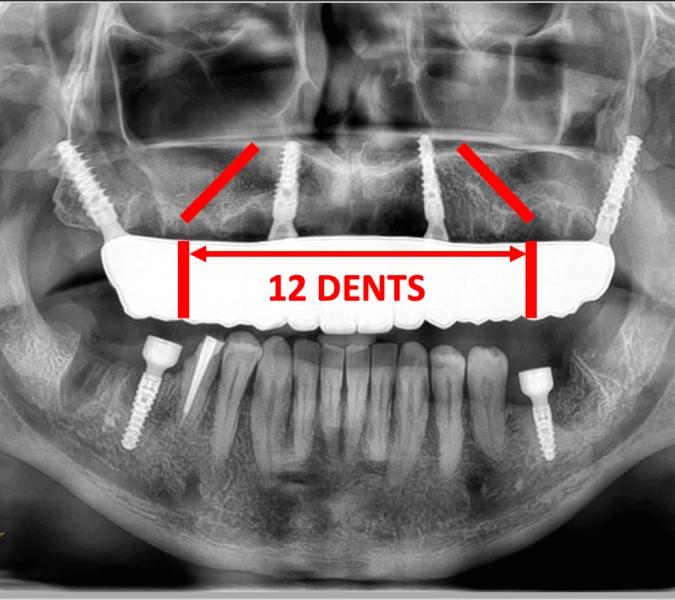

L’un des avantages majeurs de l’implant ptérygoïdien est l’ostéo-intégration rapide permise par son ancrage dans l’os cortical. Dans de nombreux cas, une prothèse provisoire peut être fixée immédiatement, offrant au patient la possibilité de retrouver une fonction masticatoire et une esthétique dès la sortie de la clinique. Cette approche, souvent combinée à la pose d’autres implants antérieurs pour les réhabilitations complètes (comme le All on 4, All on 6 ou All on 8), permet de réhabiliter l’arcade complète de manière efficace. Après une période de guérison, la prothèse définitive est installée, assurant une stabilité prothétique durable et un confort optimal.

Que vous souffriez d’un édentement postérieur partiel ou total, l’implant ptérygoïdien peut faire partie d’une solution de réhabilitation complète. Nous intégrons souvent cette technique avec d’autres implants pour reconstruire des arcades dentaires complètes. Que ce soit pour un All on 4, All on 6, All on 8, ou simplement pour compléter une dentition partielle, l’implant ptérygoïdien nous permet d’offrir des solutions fiables et durables, évitant la greffe osseuse évitée et le sinus lift bypass. Nous nous engageons à restaurer non seulement votre fonction masticatoire mais aussi l’esthétique et la confiance en votre sourire.